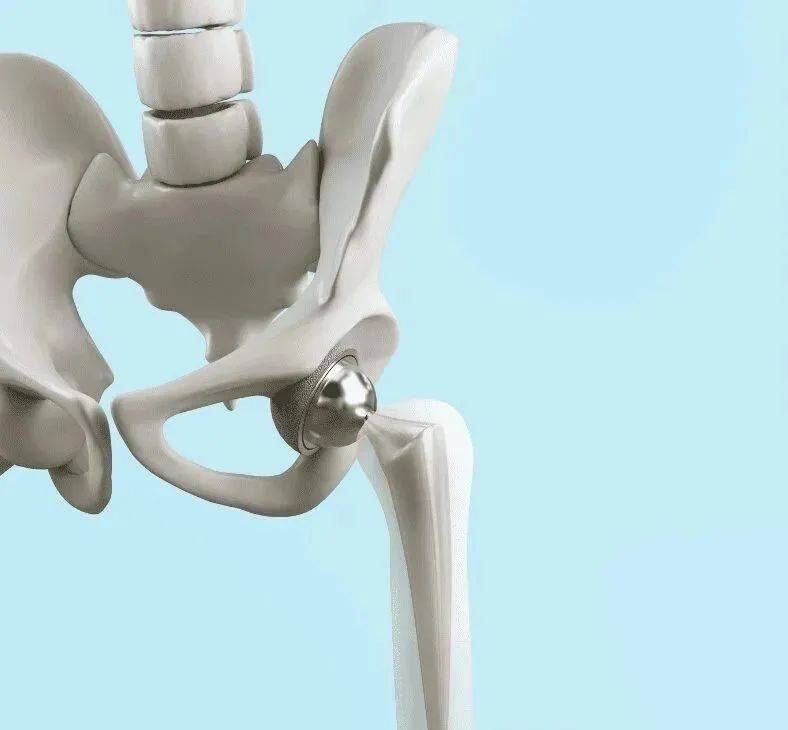

先进复合材料可制造轻质、耐用且生物相容的医疗产品。碳纤维、玻璃纤维和先进聚合物等复合材料可用于假肢、手术器械、助听器、牙科植入物、支架、健康监测带、内窥镜器械、针和板、髋关节置换术、手术机器人和外骨骼,以提供更高效、更适合患者的医疗保健解决方案。

复合材料最早于 20 世纪 70 年代初用于医疗应用,此后得到了迅速发展和应用。据报道,罗伯特·马蒂斯于 1967 年想到了“非骨水泥等弹性髋关节柄”,作为约翰·查恩利爵士金属髋关节植入物的替代品。这种等弹性髋关节柄是一种由聚甲醛共聚物制成的复合假体,于 1973 年首次植入。最初,复合材料的使用受到成本和制造复杂性的限制。然而,随着技术的进步,这些材料变得更加可行,复合材料开始用于假肢、手术器械和成像设备。

假肢和矫形器中的先进复合材料

先进复合材料可广泛用于假肢和矫形器,如夹板、鞋垫、支架、脊柱护套和头盔。其他应用包括膝关节和髋关节置换、导管、手术网、医疗器械、缓释药丸壳、植入物等。碳纤维、玻璃纤维和其他复合材料的创新使用创造了更具弹性、更持久和更有效的辅助器具,大大提高了用户的生活质量。这一进步标志着技术进步和向更加个性化和响应迅速的医疗保健解决方案迈出的一大步。

复合医疗器械的未来潜力巨大,可探索再生医学和个性化医疗器械。Nobio抗菌修复材料等复合材料的开发正在兴起,这些复合材料释放出具有强大、集中静电应力的颗粒,可在牙科应用中杀死细菌和病毒。此外,高性能聚合物(如Magnolia Trinity PEEK,于 2023 年 10 月首次用于制造医疗器械)结合了碳纤维、羟基磷灰石和聚醚醚酮。这种强大的材料组合可提供结构支撑,促进骨骼生长,并抵抗关节置换和假肢中的磨损。